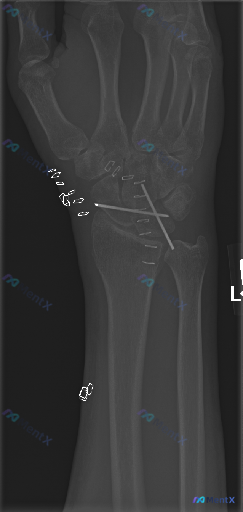

整理到一张左侧拇指的术后X光片,先放一下基础影像信息: - 部位:左侧拇指(正位) - 背景:有近期骨科手术史 - 常规报告印象:第一掌骨基底部可见内固定(克氏针)在位,未见新发骨折征象或内固定失效表现 不过这份深度分析报告里提了几个不一样的视角,甚至说「不是单纯的正常术后复查」。 想先问问大家:只...

整理到一份左腕术后的复查影像资料,想和大家讨论一下当前的优先级判断方向。 基本背景:左腕创伤术后,本次复查左手腕正位X光片。 影像所见: 1. 内固定物:舟骨腰部可见一枚金属螺钉,位置大致沿舟骨长轴;第一掌骨基底部与大多角骨附近可见两枚交叉克氏针,针尾部延伸至软组织外/影像边缘。 2. 骨折与骨骼:...

整理到一份左侧腕关节正位X线的影像资料,情况如下: - 患者有腕骨骨折手术史 - 影像显示舟骨与月骨区域有交叉克氏针内固定,针尾位于桡侧软组织内 - 舟骨及相关腕骨的骨皮质轮廓尚完整,因金属伪影遮挡,隐匿性骨折线排查受限 - 桡侧皮下及近端软组织内可见散在多个小点状高密度影 - 腕骨间排列尚可,桡腕...

整理了一份左手拇指区域的斜位X光病例资料,先把客观影像表现放出来: - 可见左手拇指近节、远节指骨及第一掌骨,第一腕掌关节、掌指关节、指间关节对位尚可,关节间隙宽度尚可 - 第一掌骨桡侧近基底部区域有一枚金属克氏针影,穿过第一掌骨,针尾弯曲并带有固定装置,从皮下穿出或止于皮下软组织层 - 克氏针穿行...

整理了一份左手拇指术后复查的影像资料,先看第一印象: - 左手拇指斜位X光,第一掌指关节(MCP)有两枚克氏针固定,穿过近节指骨基底到第一掌骨头 - 骨折线处可见骨痂形成,骨皮质尚连续,没看到明显骨质破坏或脱位 - 周围软组织没报明显弥漫性肿胀,籽骨位置也正常 报告首先提示是“术后修复状态”,但这份...